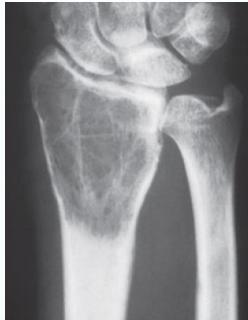

Osteochondroma (Exostosis)

- A common lesion

- Ends of long bone

- Bony overgrowth:

- Away from epiph. plate

- Covered by cartilage

- Growth:

- Stops when epiphysis close

- If continues later:

- ? Malignant transformation

Source: radiopaedia.org, Apley’s System of Orthop. And Fractures